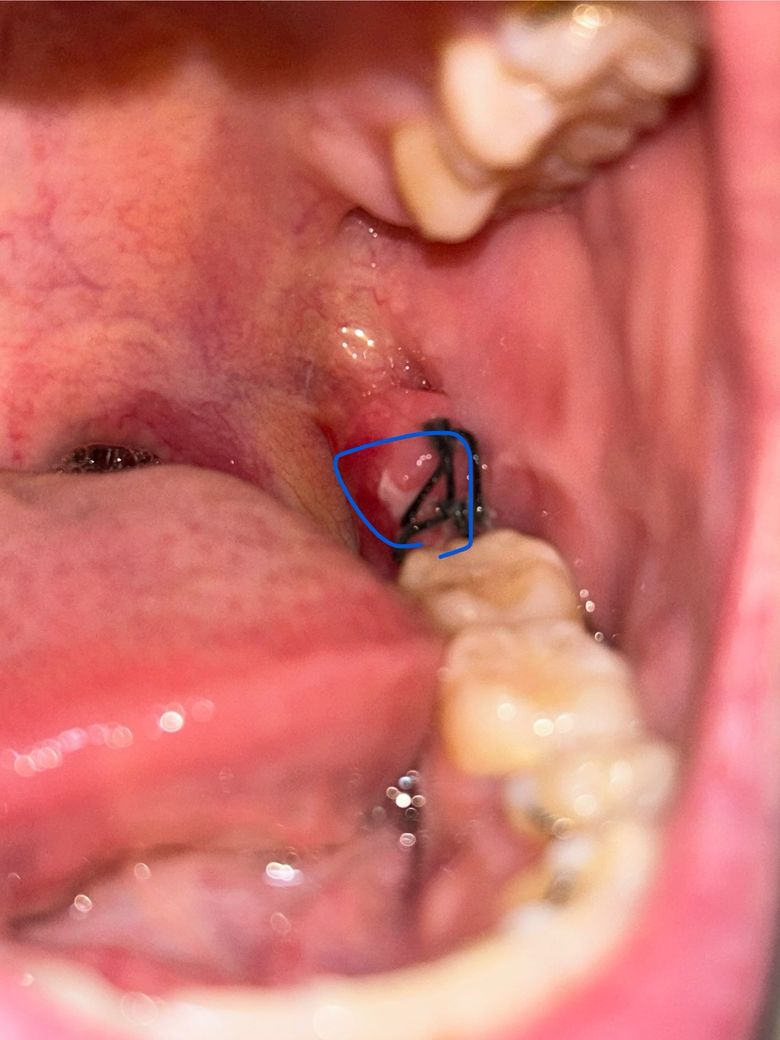

사랑니 발치 후 4일차 잇몸에 하얀게 생겼어요

8월 9일 토요일에 왼쪽 아래 사랑니 발치후 현재 4일차입니다.

붓기는 나아지고 있는 것 같은데 잇몸에 하안게 퍼지는 것 같아요..

심각한 통증이나 그런건 없는데 염증인가요? 아님 치유과정 중 하나일까요..ㅠㅜ

• 1번 째 사진

사랑니를 발치 한 이후에 회복되는 과정에서 하얗게 막이 생기는 것은 정상적인 반응입니다.

사랑니를 발치하고 나면 발치한 부위가 아물면서 하얀색 가피 등이 형성될 수 있습니다. 이런 가피는 크게 문제가 되거나 하진 않기 때문에 걱정하지 않으셔도 되며 억지로 제거하려고 하지 않는 것이 좋습니다.

사진상으로 보면 발치한곳이 잘 아물고 잇는거 같습니다. 크게 걱정하실필요는 없을것같습니다.